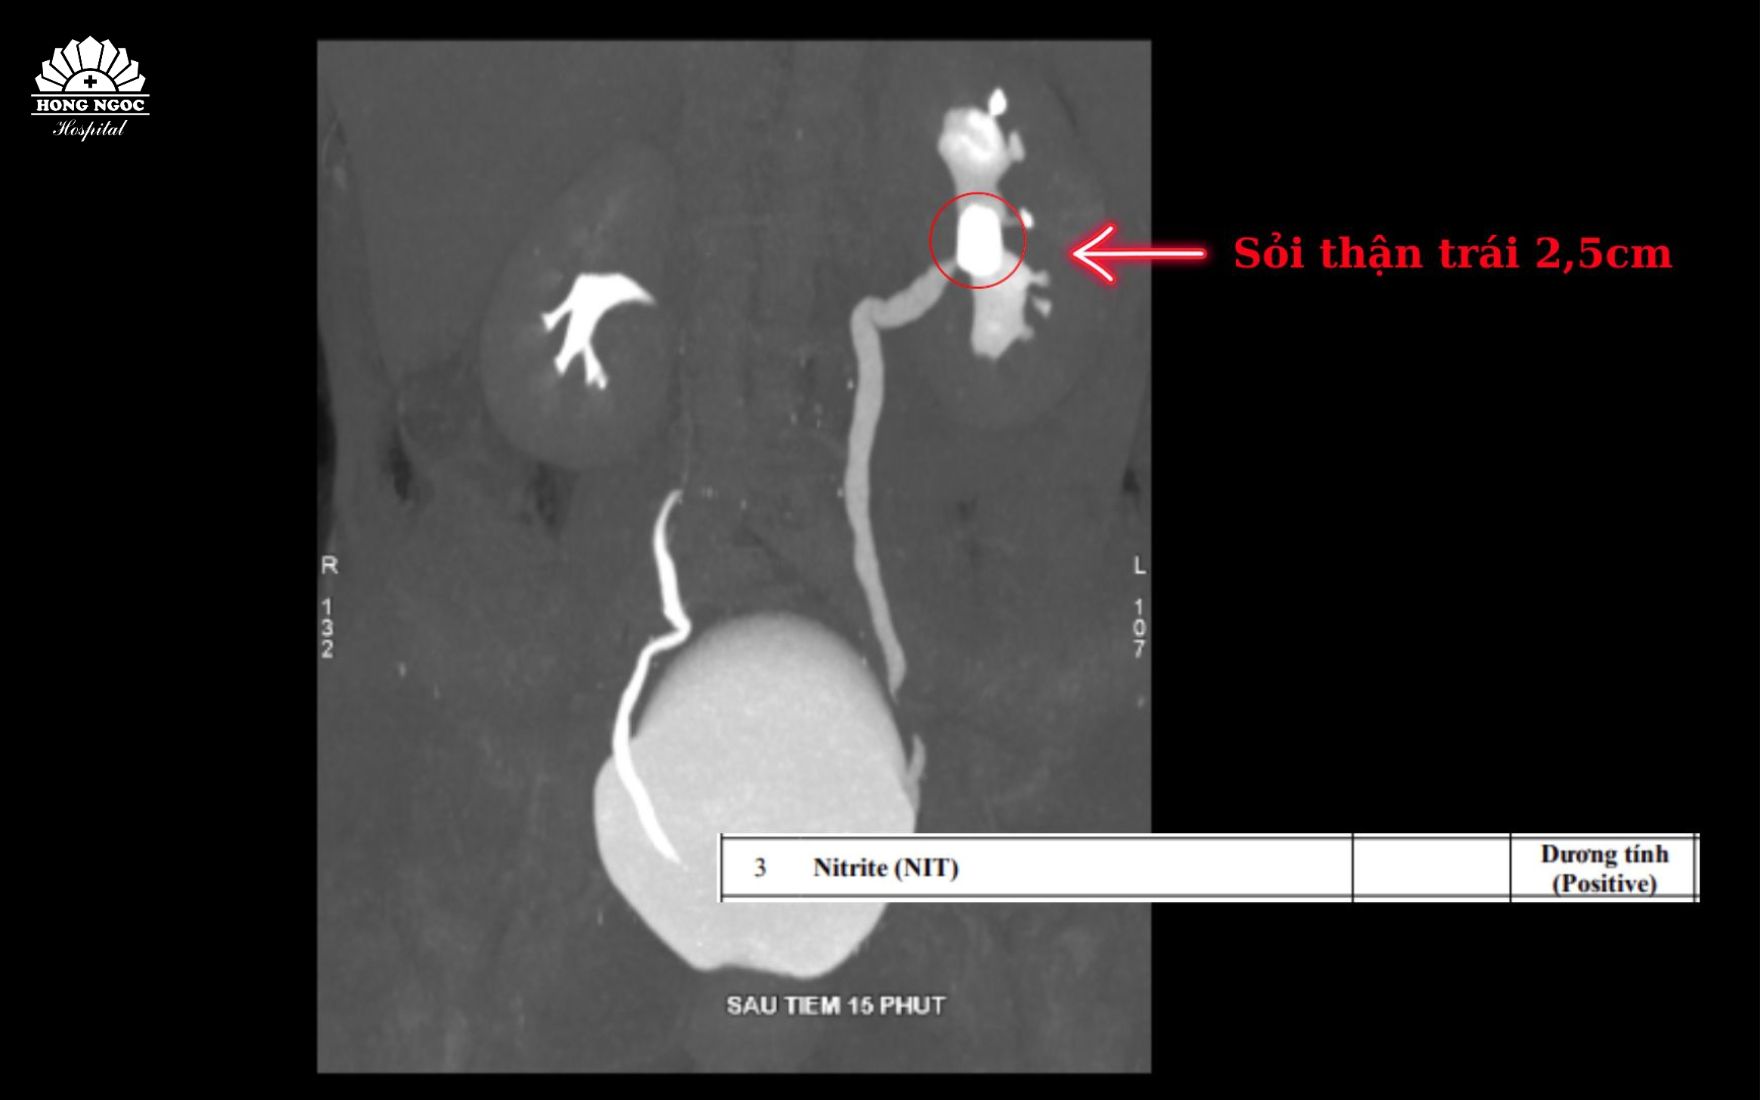

Bà H. vào BVĐK Hồng Ngọc trong tình trạng sốt cao, rét run, đau dữ dội vùng hông lưng phải. Sau khi tiếp cận quy trình cấp cứu chuyên khoa và được thực hiện các xét nghiệm, chẩn đoán hình ảnh cần thiết (siêu âm, CT-Scan), bệnh nhân được xác định có một viên sỏi kích thước lớn đến 2,5cm nằm trong đài bể thận bên trái. Đây là nguyên nhân gốc rễ gây ra tình trạng đau lưng kéo dài cho bệnh nhân, từ đó biến chứng nhiễm trùng đường tiết niệu và ứ mủ thận trái, khiến bệnh nhân phải nhập viện cấp cứu.

Sỏi thận kích thước lớn kèm nhiễm khuẩn đường tiết niệu